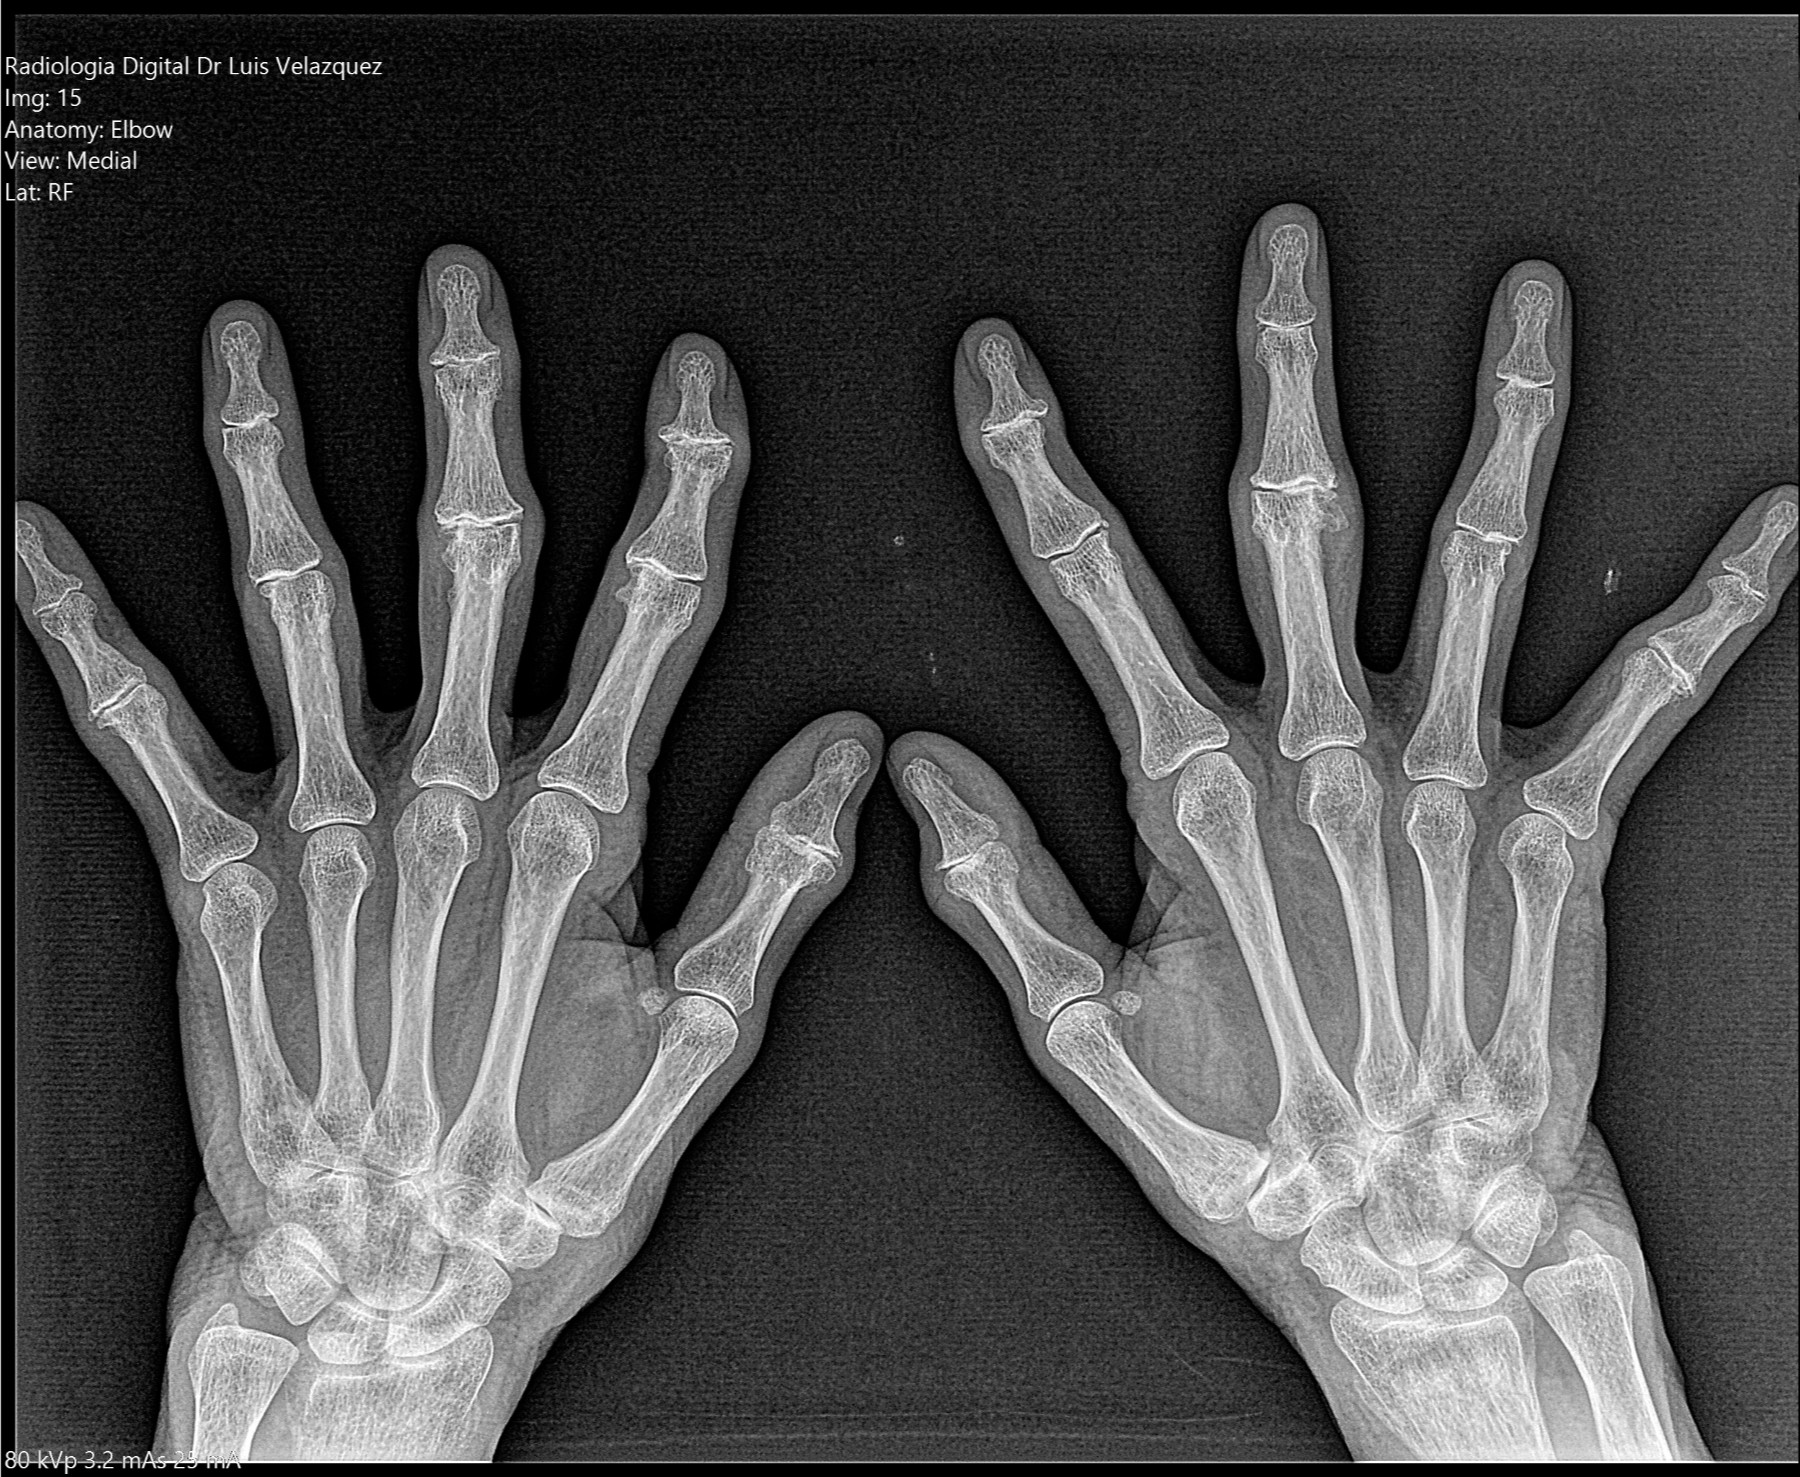

Radiología Digital como Herramienta Complementaria en el Dictamen de Bienes Muebles

Desde el descubrimiento de los rayos “X” y las placas radiográficas por Wilhelm Conrad Roentgen y su posterior difusión a través de la Asociación Físico médica de Wurzburg el 28 de diciembre de 1895, que fue la primera asociación que habló de los nuevos rayos que podían penetrar el cuerpo y fotografiar los huesos, ha habido muchos cambios tanto en la forma de obtener, procesar e incluso en la forma de visualizar, manejar y almacenar las placas radiográficas.